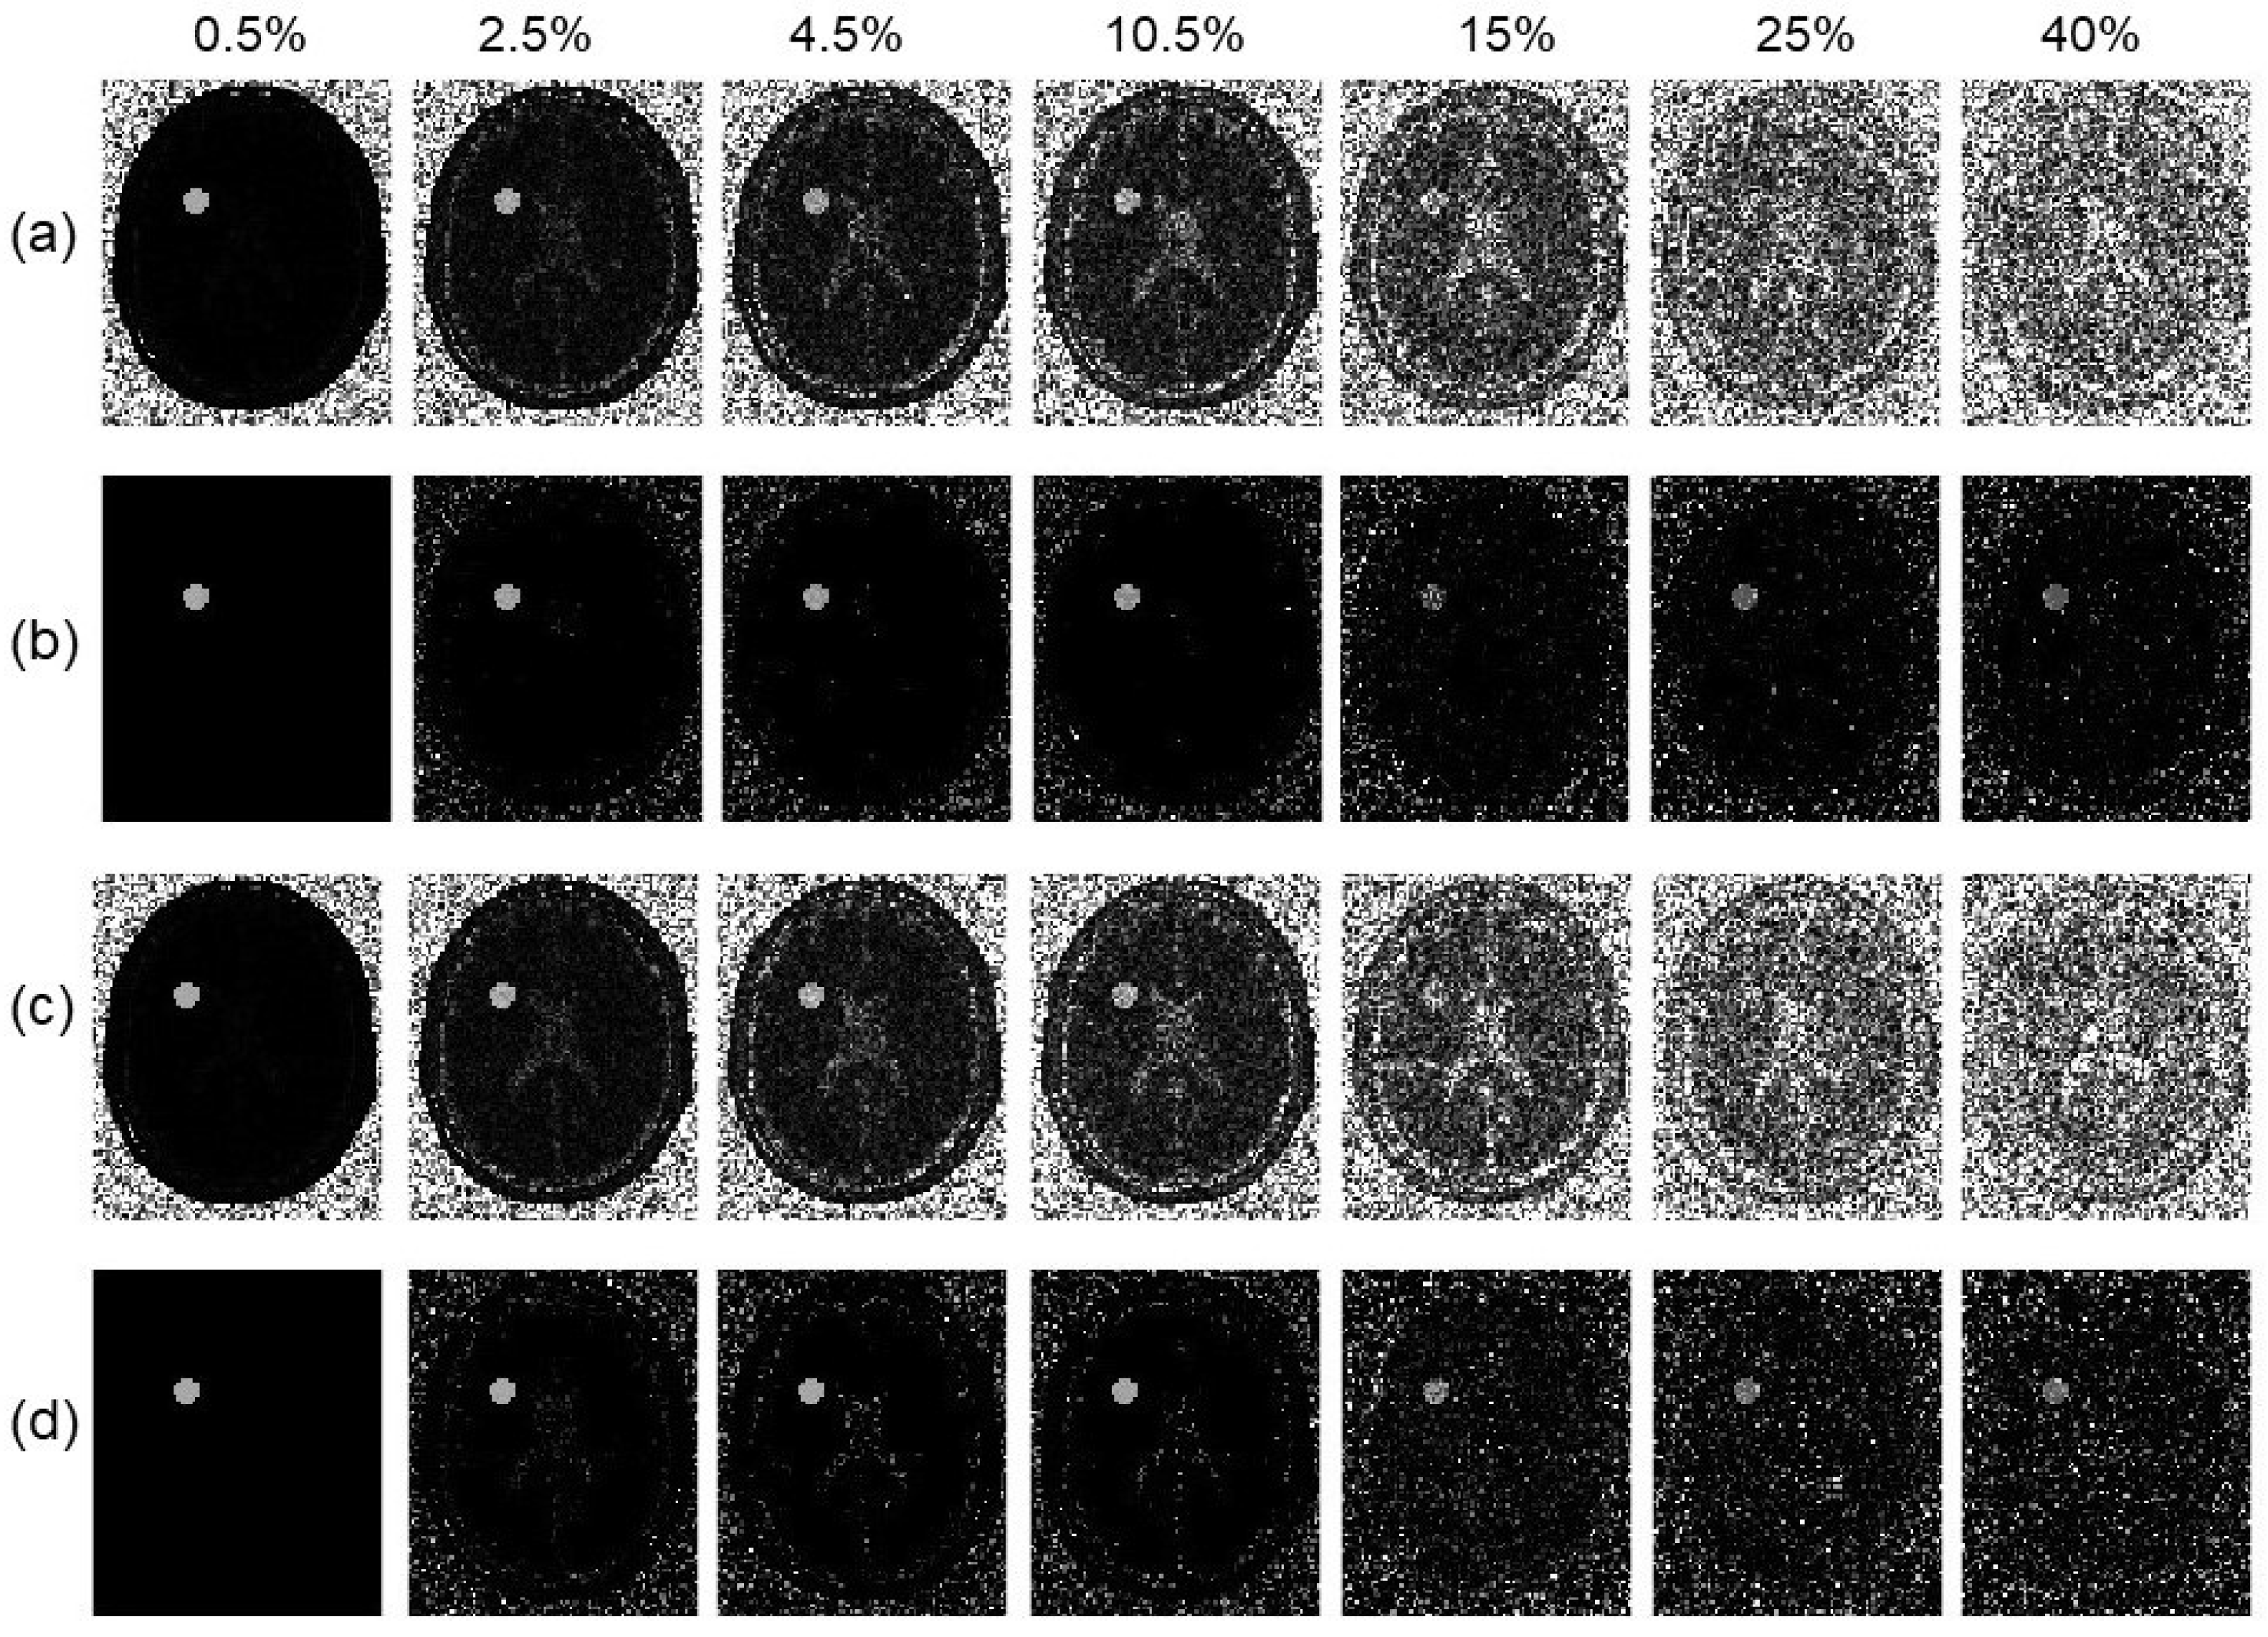

3.5. Reduction in Number of Offset Frequencies